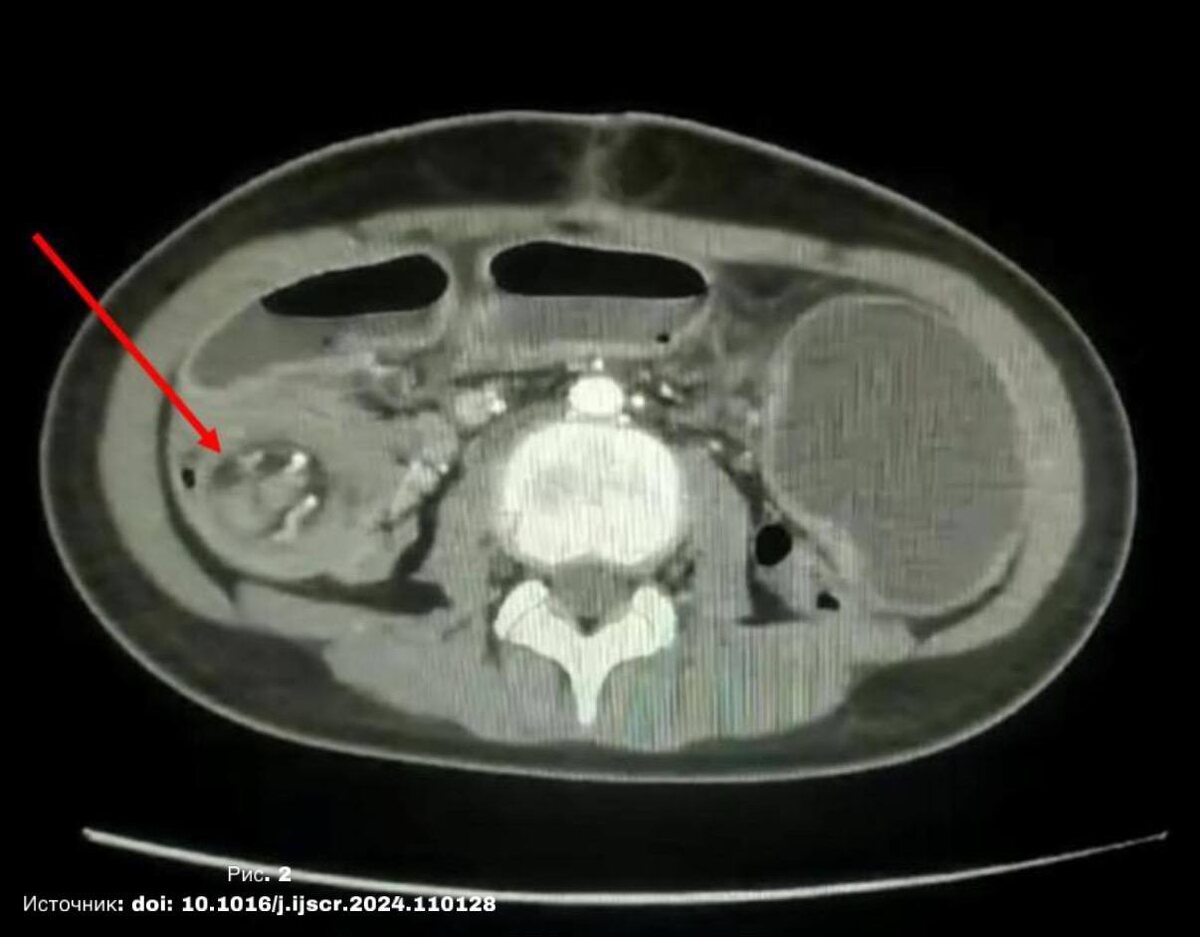

🔵КТ ОБП см. на рис. 2

Подвздошно-ободочная инвагинация, полип в 80 см от последней подвздошной петли